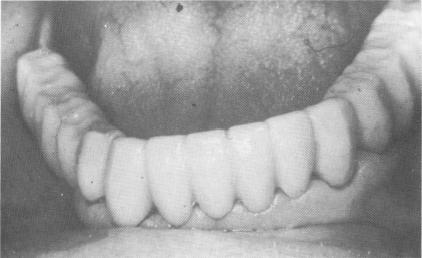

Fig. 11-54. The temporary acrylic splint.